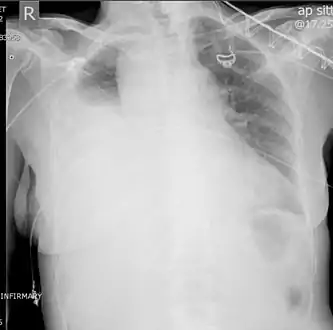

Chest X-ray

Development of hemothorax following lung lesion biopsy

Showing a massive left-sided hemothorax

Right showing a massive right hemothorax

A chest X-ray is the most common technique used to diagnosis a hemothorax.[23] X-rays should ideally be taken in an upright position (an erect chest X-ray), but may be performed with the person lying on their back (supine) if an erect chest X-ray is not feasible. On an erect chest X-ray, a hemothorax is suggested by blunting of the costophrenic angle or partial or complete opacification of the affected half of the thorax. On a supine film the blood tends to layer in the pleural space, but can be appreciated as a haziness of one half of the thorax relative to the other.[5] A small hemothorax may be missed on a chest X-ray as several hundred milliliters of blood can be hidden by the diaphragm and abdominal viscera on an erect film. Supine X-rays are even less sensitive and as much as one liter of blood can be missed on a supine film.[24]